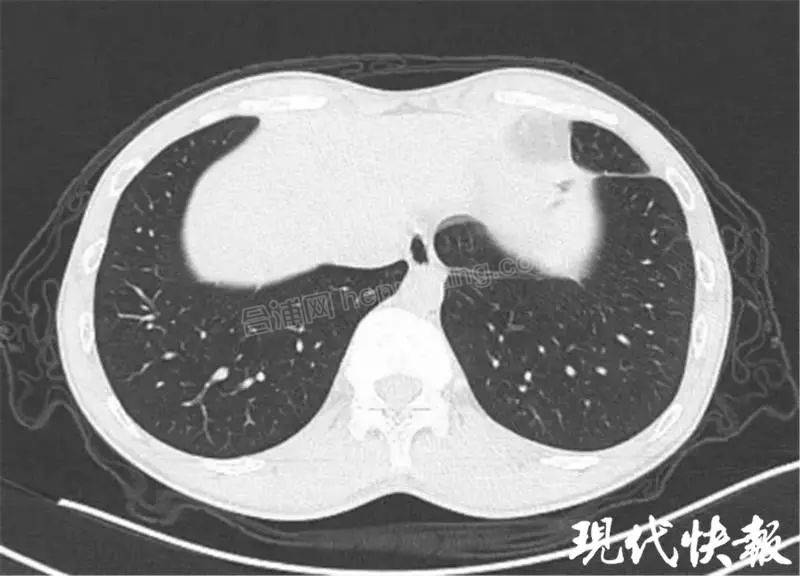

微信图片_20200428111310.jpg

肺吸虫患者典型的 " 隧道征 ”↑↑↑

记者了解到,肺吸虫病的致病作用主要是由童虫、成虫在组织器官中移行、窜行、定居及分泌物、代谢产物所引起,可累及肝脏、肺、胸、腔、眼、脑、皮下组织等多个组织、器官。换句话说,这些小虫一旦进入人体后,就会在组织器官中到处乱钻,并产生分泌物、代谢产物,时间长了以后,甚至能在肺部钻出一个个 " 隧道 ",形成肺纤维化。再加上这种疾病的临床表现复杂多样,缺乏特异性,极易造成误诊,更是增加了诊断的难度。